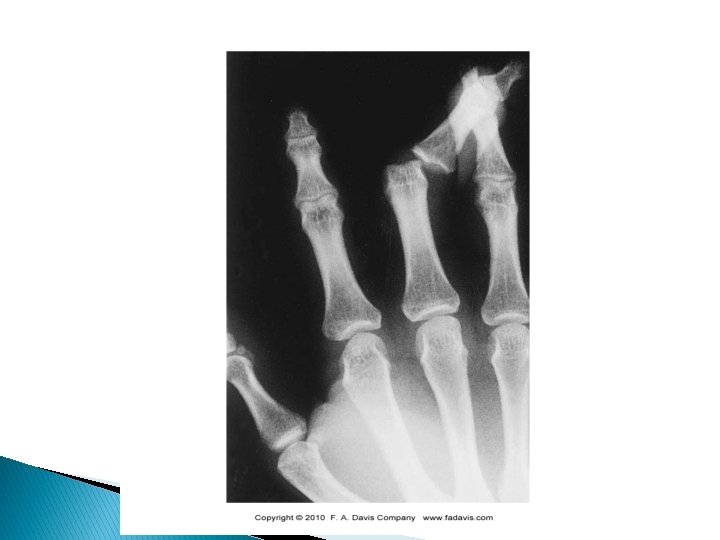

Boutonniere Deformity � Extensor ◦ ◦ ◦ Tendon Rupture Characterized by flexion of the PIP joint and hyperextension of the DIP joint Injury to the central slip of the extensor digitorum tendon at the PIP joint from forceful flexion (“Buttonhole rupture”) Signs and symptoms � � Localized pain and swelling over middle phalanx Point tenderness near the tendon insertion Weakness with extension of the PIP joint will be flexed; DIP joint is hyperextended

Boutonniere Deformity